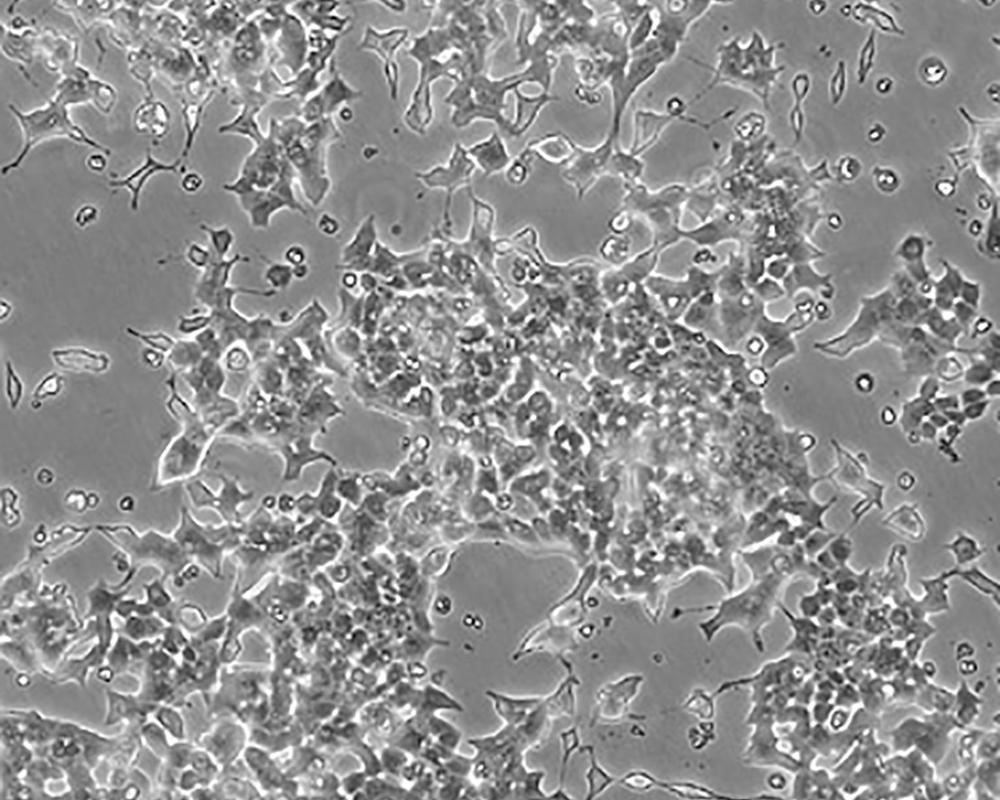

Beta-TC-6

中文名稱 小鼠胰島素瘤胰島β細胞

組織來源 胰島素瘤

形態特征 epithelial

細胞描述 這株細胞來源于轉基因小鼠中生長的一個胰腫瘤(胰島素瘤)。這種小鼠攜帶了大鼠胰島素II基因啟動子調控的SV40早期基因的假基因結構。細胞包含豐富的胰島素和小量的胰高血糖素及生長抑素。響應葡萄糖而分泌胰島素